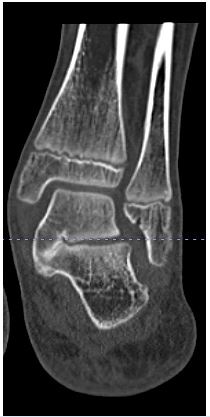

Radiographic evaluation of deformity correction included measurement of the calcaneal pitch angle (normal range, 18°–32°), Meary’s angle (normal range, –4° to +4°), and talonavicular coverage angle (normal, < 7°) [10,11]. Coalition was confirmed radiographically with CT (Figure 1). Hindfoot valgus was measured on coronal CT reformats, with a valgus angle greater than 16° considered the threshold beyond which isolated RC was not recommended [6,12,13].

Figure 1: CT scan conformation of talo-calcaneal coalition with hindfoot valgus.